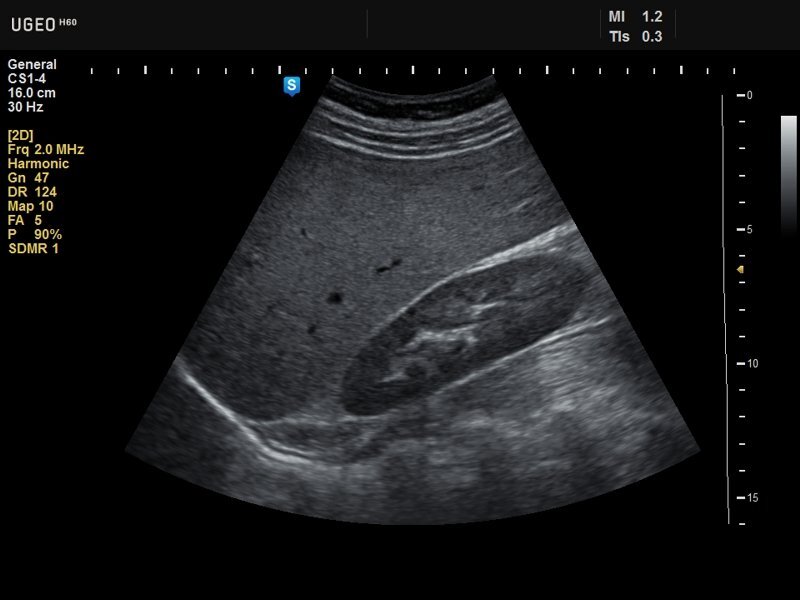

Сонограммы стали проще

Сонограммы сердца могут помочь диагностировать такие состояния, как ревматическая болезнь сердца, от которой ежегодно умирают 1,4 миллиона человек, но во многих бедных странах нет ультразвуковых аппаратов и технических специалистов, обученных их использованию.

И тут в помощь приходит программное обеспечение машинного обучения

Caption AI. Caption AI, предназначенное для работы с портативными ультразвуковыми устройствами нового поколения, помогает специалистам выполнять небольшие настройки, необходимые для получения изображения сердца, которое затем врач может исследовать на предмет потенциальных проблем. «Вы не можете отправлять каждого человека к кардиологу каждый год», - говорит Килиан Кёпселл, соучредитель и технический директор Caption Health. «Но вы можете регулярно проходить осмотр у своего лечащего врача, и с помощью этих технологий они могут обследовать вас намного лучше, чем это было возможно раньше». - Алехандро де ла Гарса